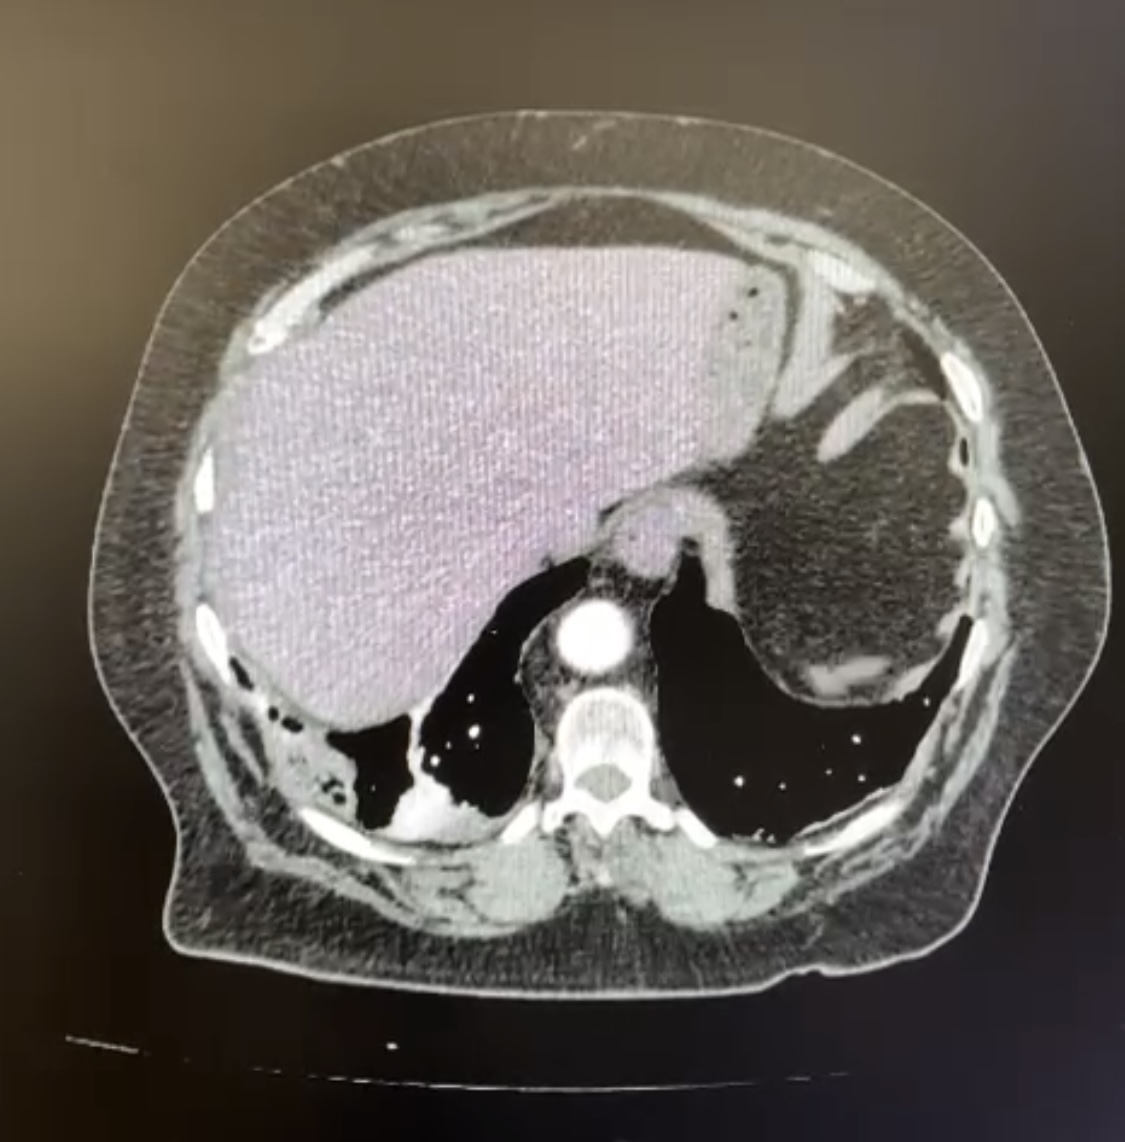

Ante estos hallazgos, movilizamos la UVI móvil y la paciente fue trasladada al hospital donde se realizó ATC de arterias pulmonares que confirmó el diagnósitco de tromboembolismo pulmonar distal bilateral y pequeñas consolidaciones periféricas en relación con infartos pulmonares (Imagen 2).